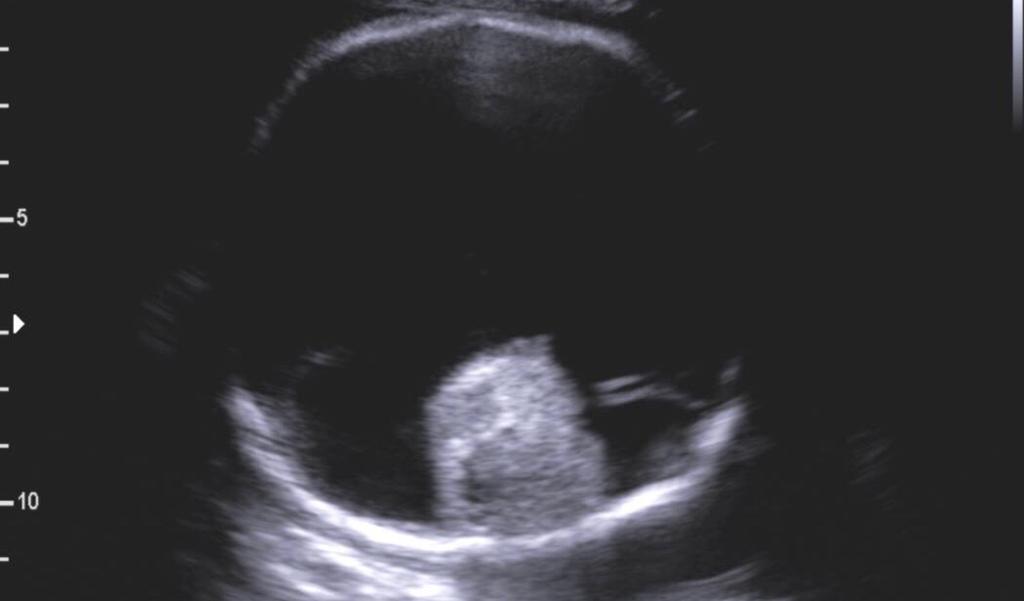

Holoprosencefalia alobar

Se caracteriza por marcados alteraciones en la línea media del encéfalo y/o malformaciones faciales.

- Fusion completa de los hemisferios cerebrales

- Ausencia de la fisura interhemisferica y de la hoz cerebral

- Holoventriculo, quiste dorsal

- Ausencia de septum pellucidum